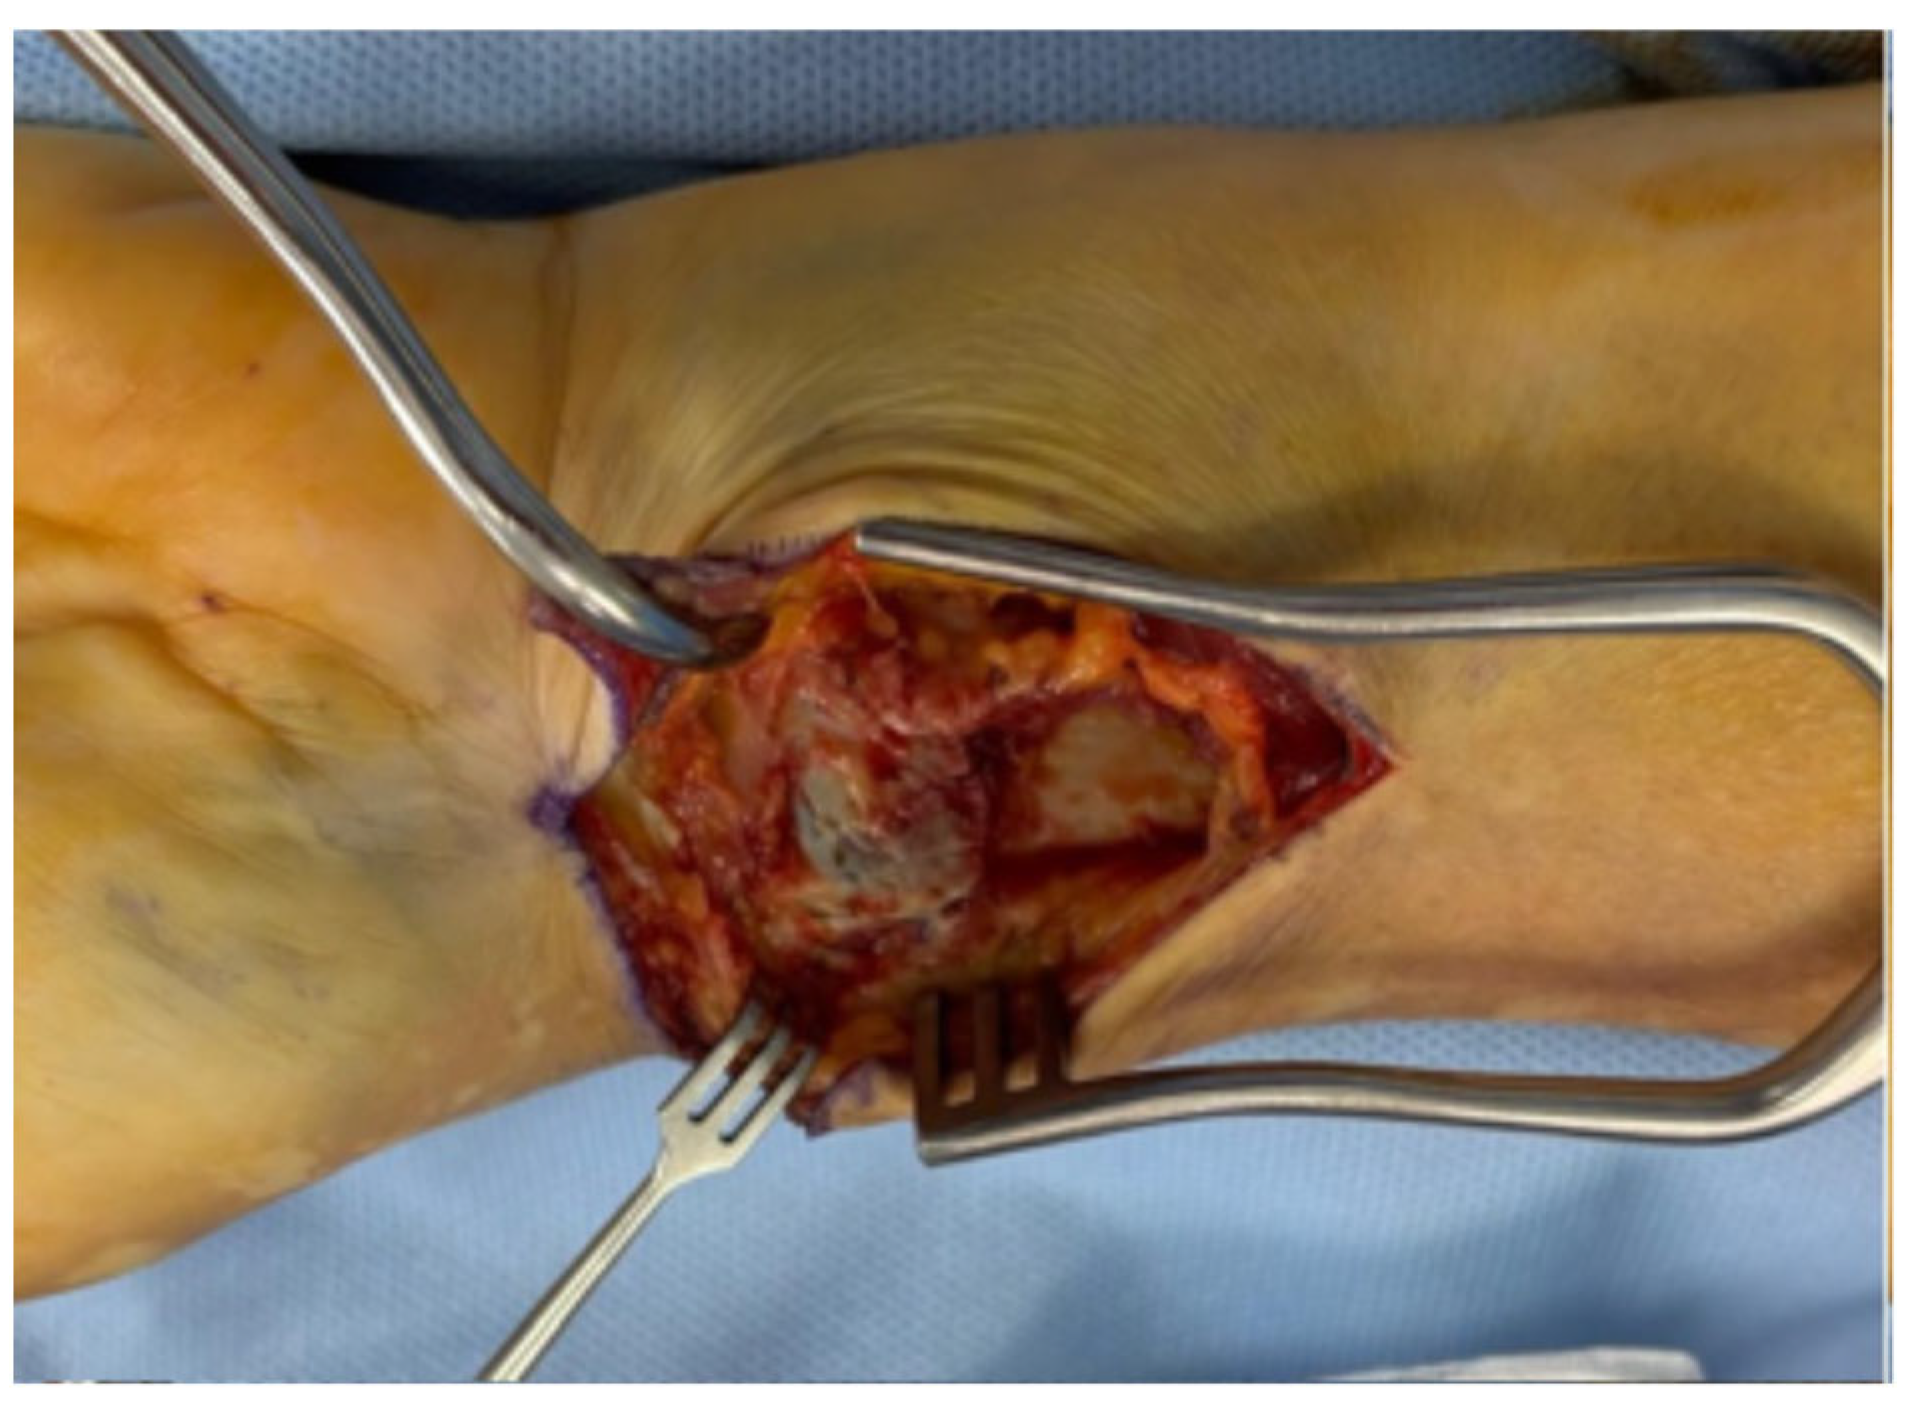

A skin incision is made directly over the flexor carpi radialis (FCR) tendon, extending approximately 6–8 cm. Distally, the incision continues in a zig-zag configuration, beginning at least 1.5 cm proximal to the radial styloid and directed towards it, with the apex of the “V” positioned near—but not directly over—the styloid process to prevent exposure of the radial artery. The distal tip of the “V” lies proximal to the wrist flexion crease, corresponding to the most distal course of the FCR tendon (Figure 1).

Figure 1. (a) Orbay incision; (b) Authors modified incision.